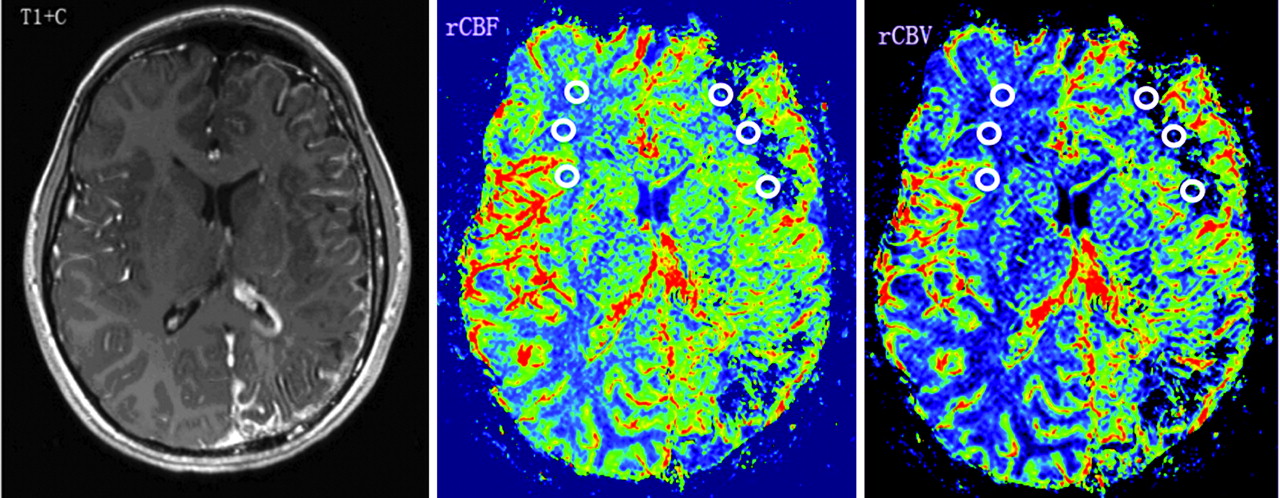

A series of perfusion parameter maps were postprocessed from MR perfusion raw data based on tracer kinetic methods,17 including rCBV, rCBF, and MTT, in SPIN software. Among these indices, rCBF values more directly and specifically reflect the blood flow status in the brain tissue. As a result, the rCBF map was chosen for comparing the cerebral perfusion between the 2 (affected versus unaffected) hemispheres. rCBF, rCBV, and rMTT values in the affected WM, defined by the presence of abnormally enhancing vessels and/or leptomeningeal venous angiomatosis, and contralateral homotopic WM were manually measured by 2 neuroradiologists. Three ROIs, 20–40 voxels, were placed on every section in the affected and contralateral WM. On the CBF map, vessels and cortex are colored red and green, respectively, and WM is colored blue, allowing for accurate placement of ROIs over WM, while avoiding inclusion of vessels, cortex, and ventricle (Fig 1). Perfusion parameters were measured in all affected regions based on abnormal features on contrast-enhanced T1WI, including leptomeningeal angioma and/or dilated transmedullary veins, the very same features used to define involvement when calculating brain atrophy ratios as described above. The final values quoted were the mean of the measurements in all affected sections, yielding hemispheric perfusion parameter AIs, calculated based on formula 2.

A 10-year-old girl with developmental delay (IQ = 55) and monthly seizures (patient 3 in On-line Tables 1 and 2). Contrast-enhanced T1WI (T1+C) shows left hemisphere volume loss and characteristic leptomeningeal enhancement in the same region, as well as a prominent left choroid plexus. PWI demonstrates decreased rCBF and rCBV (CBF-AIs = −0.67, CBV-AIs = −0.52) in the left frontal and occipital WM regions, underlying the leptomeningeal angiomatosis. Regions of interest placed on the affected left frontal WM and contralateral homotopic region are demonstrated.

In the SWS group, CBF-AIs varied between −0.82 and +0.39, whereas CBV-AIs varied between −0.67 and +0.69. All CBF-AIs values were considerably outside the normal range (the smallest AI was −0.12, consistent with a 12% asymmetry), and patients were divided into 2 subgroups according to their CBF-AIs values: an rLP group (negative CBF-AIs, indicating abnormally low perfusion on the angioma side; n = 9; Fig 1) and an rHP group (positive CBF-AIs, increased perfusion on the angioma side; n = 5; Fig 2). Detailed results are listed in On-line Table 2. It should be noted that 4 of the 5 children with high perfusion had a history of seizures, but all 4 were free of clinical seizures for at least 4 months before the MR imaging scan.